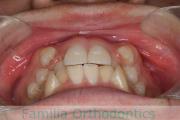

No.22V-409

- 叢生

- 16歳

- 女性

- 上:

- 44

- 下:

- 8|58

- 主な使用装置:

- FEA

- 治療にかかった費用:

- 86万円

八重歯を治したいということで来院されました。下あごの左ずれのある上顎前突(出っ歯)・叢生(でこぼこ)でしたので、上は左右から、下はで左のみ小臼歯を抜歯して、歯科矯正用アンカースクリューとマルチブラケット法にて治療を行いました。2年強、30回程度の通院が必要でした。

上下とも前歯の叢生(でこぼこ、凹凸、ガタガタ)があるため、保定を怠ると後戻りのリスクがあります。